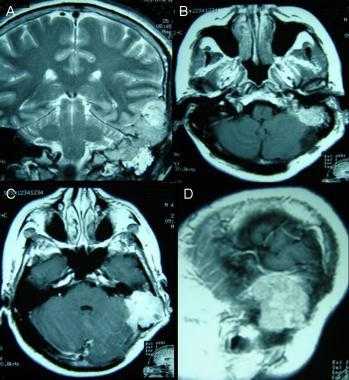

Анапластическая менингиома лобной доли. Н а КТ-изображении в режиме мозгового окна и костного окна Хаунсфильда видна крупная внутрикостная менингиома. Обнаруживаемые КТ-феномены неспецифичны и могут включать различные изменения от остеолиза до остеосклероза. Внутрикостные менингиомы составляют менее 1% опухолей костной ткани.